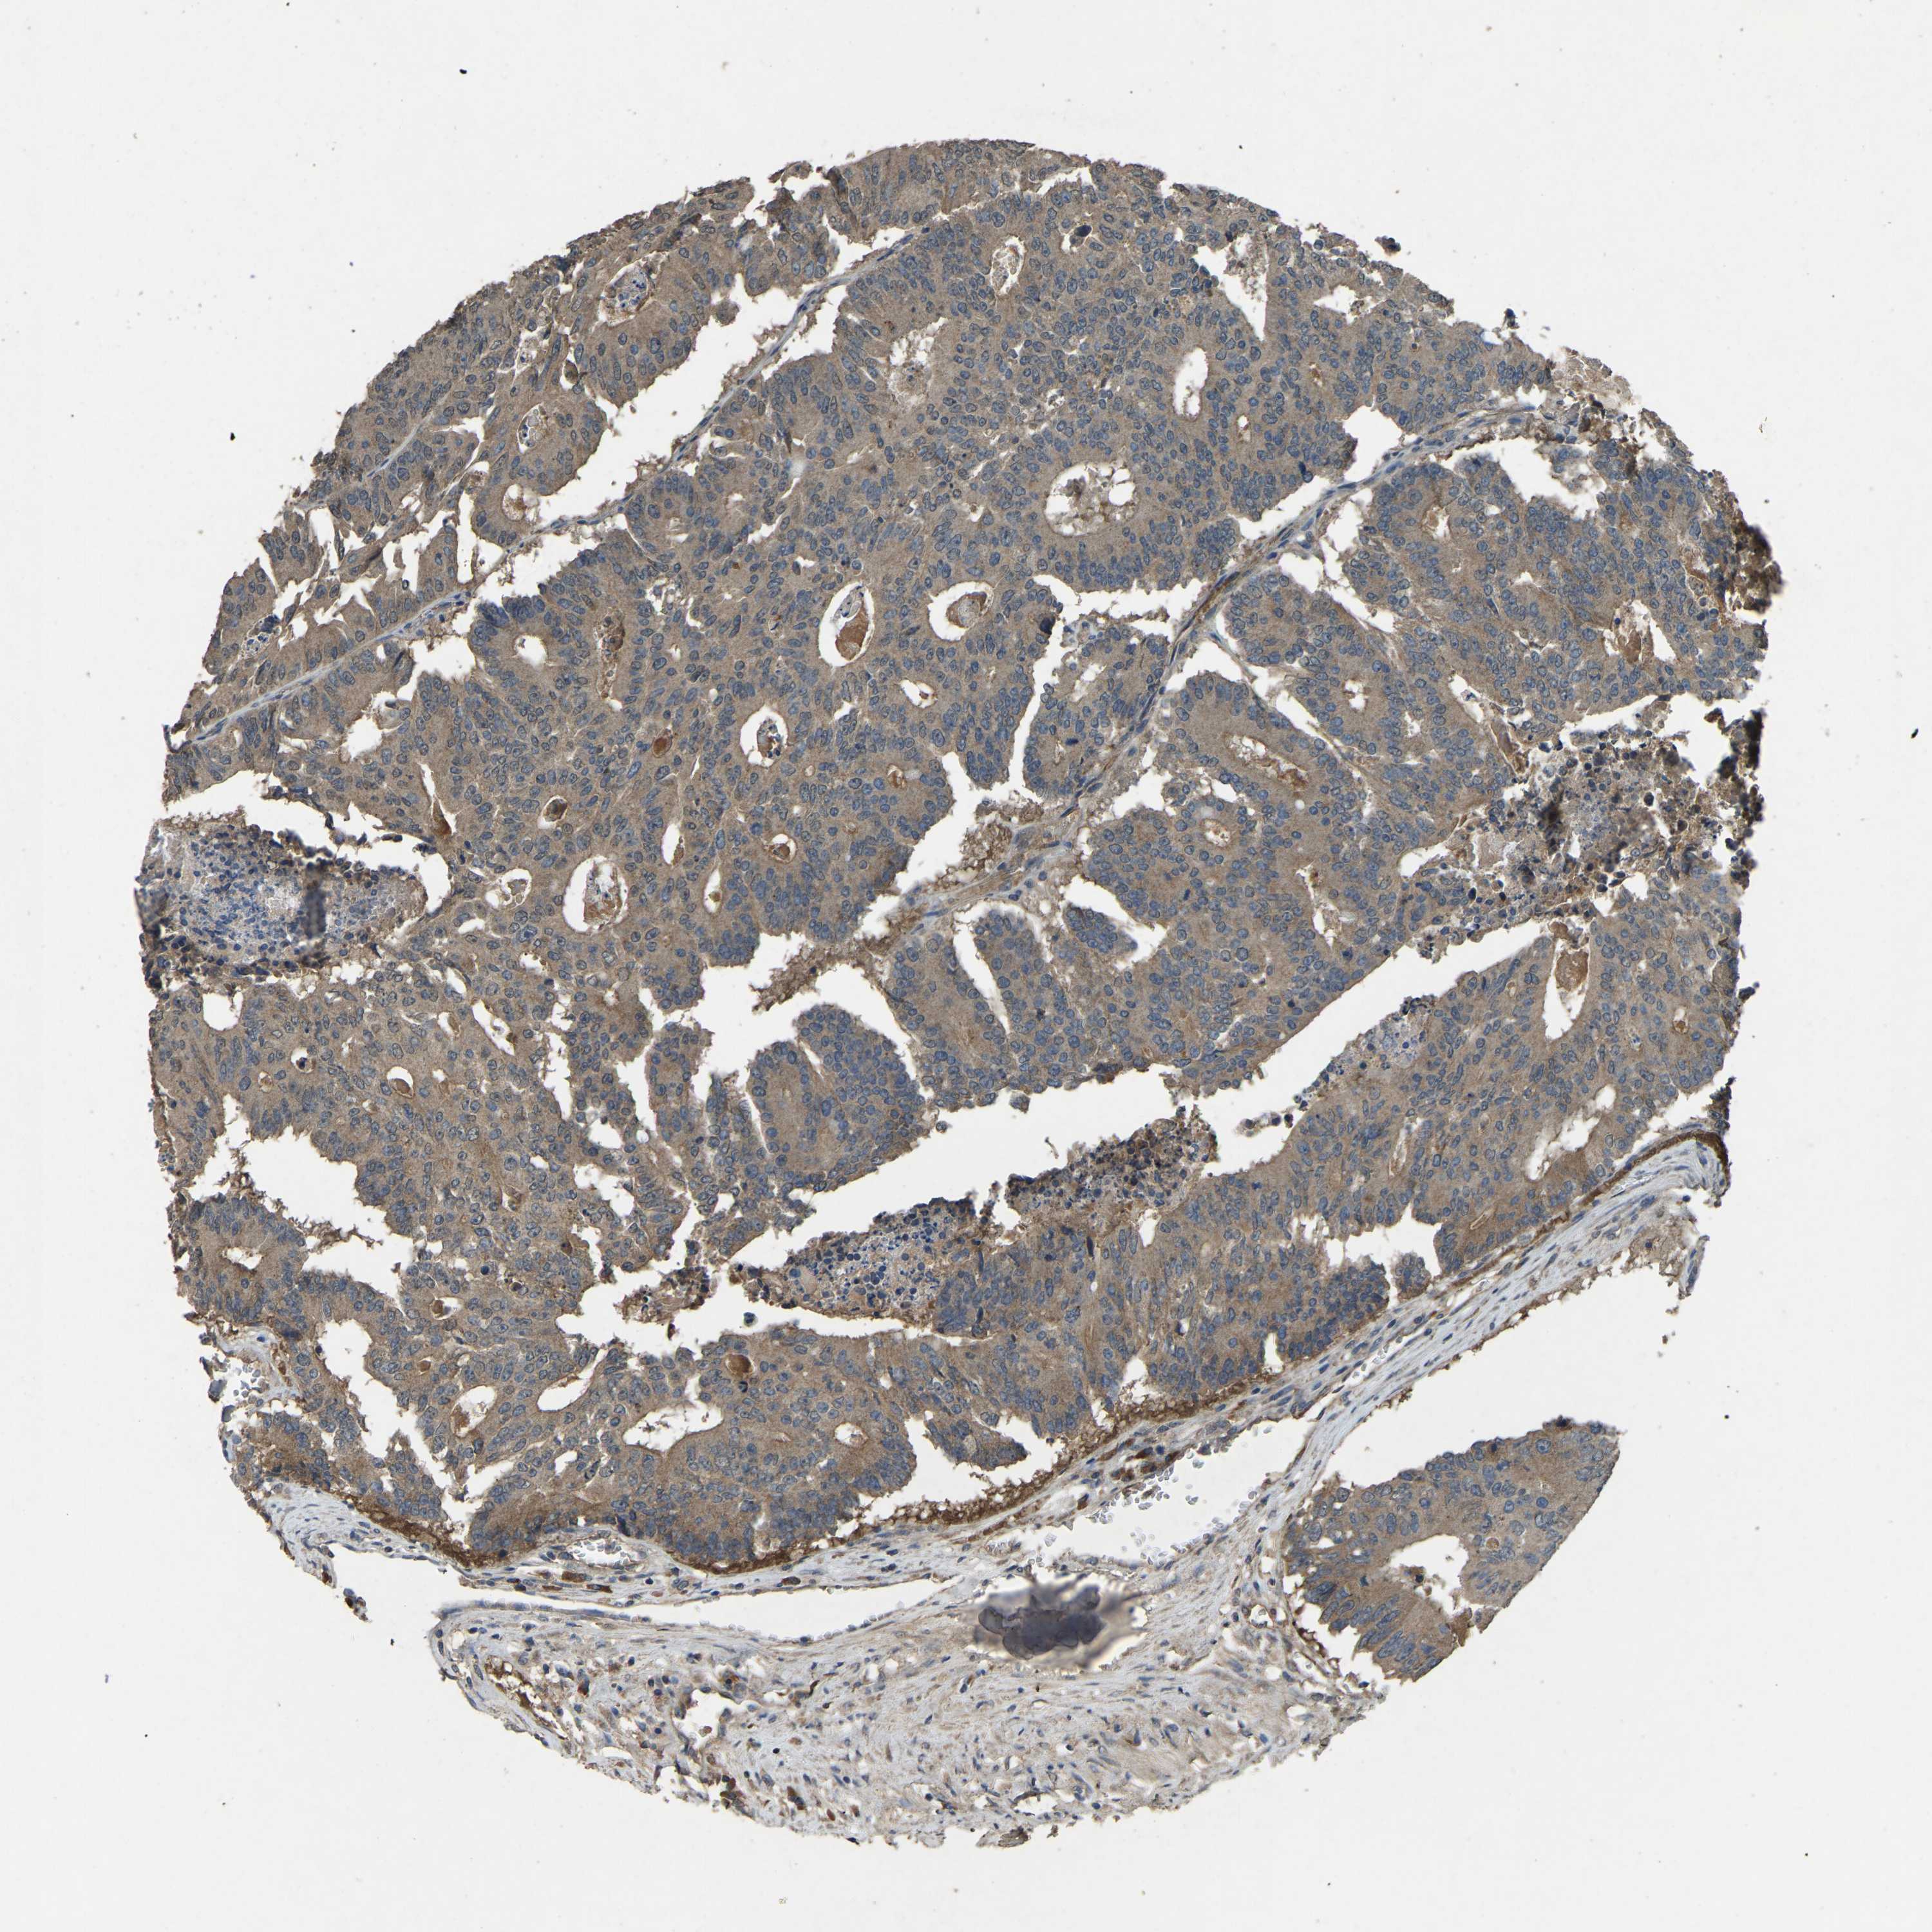

CANCER COLORECTAL CANCER Show tissue menu

Colorectal cancer

Human cancer

Colon adenocarcinoma